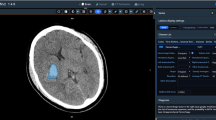

Aimed to develop a nomogram model based on deep learning features and radiomics features for the prediction of early hematoma expansion.

A total of 561 cases of spontaneous intracerebral hemorrhage (sICH) with baseline Noncontrast Computed Tomography (NCCT) were included. The metrics of hematoma detection were evaluated by Intersection over Union (IoU), Dice coefficient (Dice), and accuracy (ACC). The semantic features of sICH were judged by EfficientNet-B0 classification model. Radiomics analysis was performed based on the region of interest which was automatically segmented by deep learning. A combined model was constructed in order to predict the early expansion of hematoma using multivariate binary logistic regression, and a nomogram and calibration curve were drawn to verify its predictive efficacy by ROC analysis.

Our study revealed that the deep learning model can significantly improve the work efficiency of segmentation and semantic feature classification of spontaneous intracerebral hemorrhage. The combined model has a good prediction efficiency for early hematoma expansion.

• We employ a deep learning algorithm to perform segmentation and semantic feature classification of spontaneous intracerebral hemorrhage and construct a prediction model for early hematoma expansion.

• The deep learning radiomics model shows a favorable performance for the prediction of early hematoma expansion.